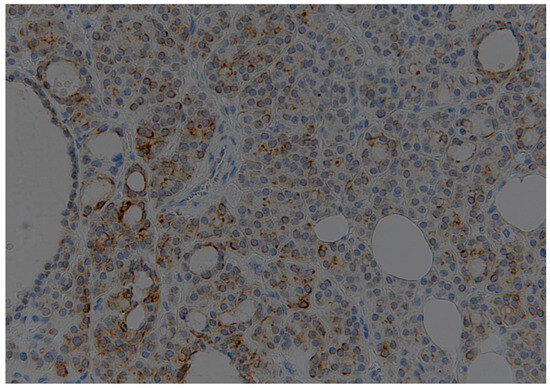

| Thyroid Cancer | +++c/focal n | +c/-n | -c/-n |

| HT | - | +c/-n | -c/-n |

| Adenomas | ++c/focal n | +c/-n | -c/-n |

| Thyroid Cancer | +c/+n | +++c/+n | +c/+++n |

| HT | - | focal c/++n | focal c/+++n |

| Adenomas | ++c/+n | +c/+n | -c/focal n |